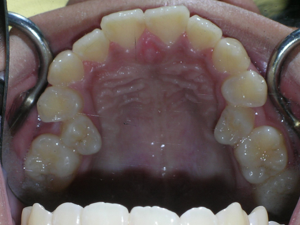

So here’s a case of an open bite, with a protrusion. There was a fair degree of crowding as well.

We decided to do porcelain brackets and have select teeth removed. Take a look.

Here are the results.